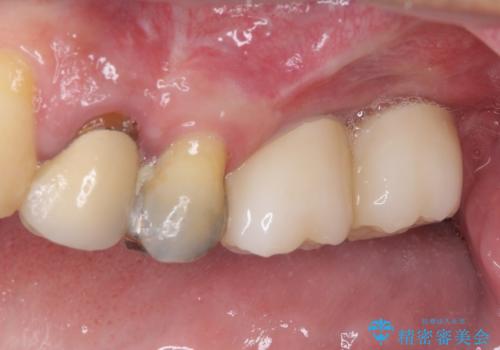

左上の奥歯は2本抜歯が必要であったため、治療期間中は右側に負担がかかり、頻繁に仮歯が壊れてしまいました。

左上に仮歯が装着されたからは咬み合わせが安定し、スムーズに治療を進めることができました。